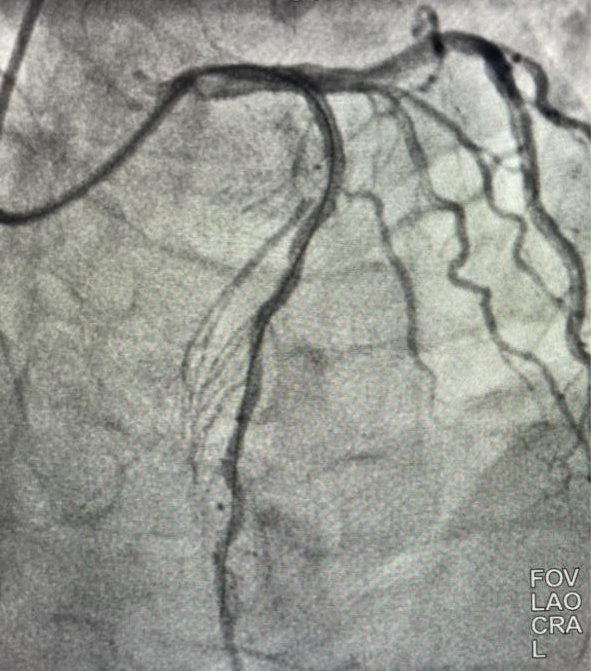

進入導管室後,立即開始消毒、鋪單、局麻、穿刺等操作(zuò),僅6分(fēn)鍾即完成冠脈造影,11分(fēn)鍾即恢複閉塞段血流,術中患者再次出現(xiàn)室顫,搶救成功,45分(fēn)鍾完成全部手術,術後患者生(shēng)命體(tǐ)征平穩,入重症監護室治療,2天後轉入普通病房(fáng),病情好(hǎo)(hǎo)轉後出院。經1個(gè)月(yuè)(yuè)随訪患者心髒功能(néng)等各項指标恢複良好(hǎo)(hǎo)。